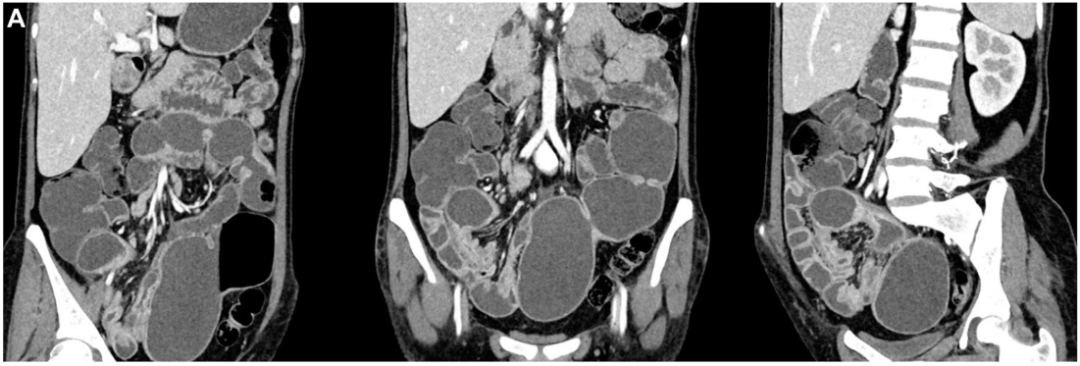

病史摘要:30岁男性,因“上腹不适6月,腹胀20天”入院。6月前无诱因出现上腹部不适、进食后腹胀,外院胃镜示反流性食管炎,肝功异常,对症治疗缓解。20天前出现全腹胀、黄疸、食欲降低、双下肢水肿。既往青霉素过敏,有吸烟、饮酒史,曾长期在高原工作。 诊疗过程:入院查体生命体征平稳,全身皮肤巩膜黄染,腹部膨隆,移动性浊音阳性。辅助检查提示布加综合征、肝硬化等。诊断为慢加急性